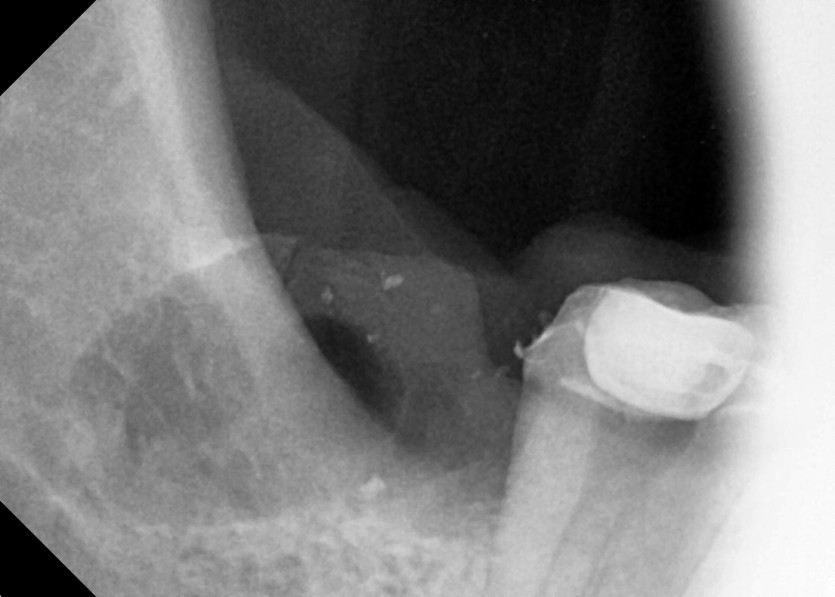

#18,48 사랑니 발치

구강 외과 전문의가 당일 발치했습니다.